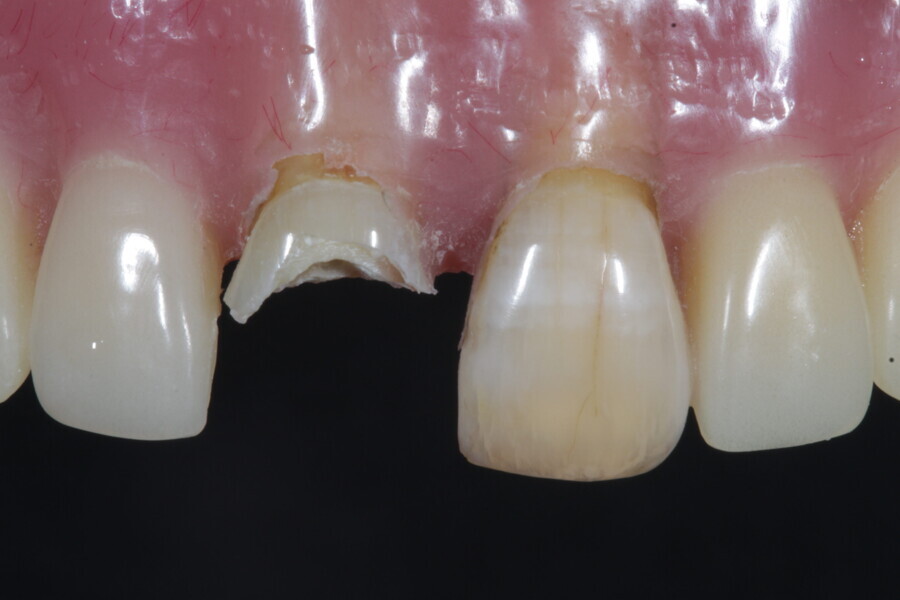

1. functional and aesthetic reconstruction of a maxillary anterior tooth using fibre-reinforced flexible micro-posts after endodontic treatment (Figs. 3–20);

Example 1—showing functional and aesthetic reconstruction of a maxillary anterior tooth using fibre-reinforced flexible micro-posts after endodontic treatment.